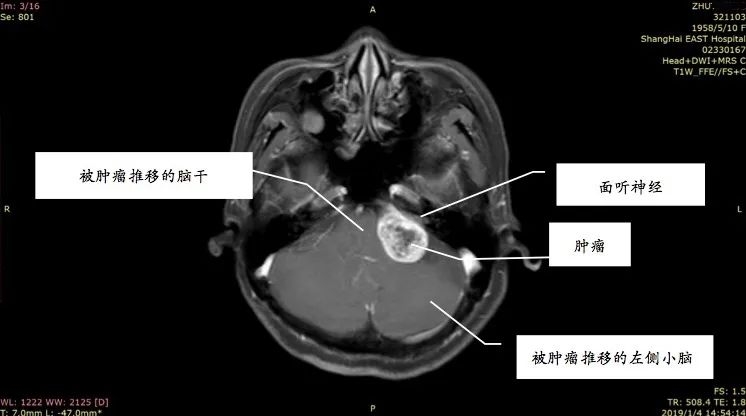

姚先生打电话时总听不清对方讲话,右边耳朵像有蜜蜂在飞,发出嗡嗡的声音。起初并没太在意,以为是工作繁忙劳累或情绪紧张,休息一会儿也就好了。前段时间他感觉耳鸣越来越厉害,并且还出现听力下降、失眠等症状,到医院做了头部的核磁共振增强扫描,发现他患上了听神经瘤。

听神经瘤是指起源于听神经鞘的肿瘤,为良性肿瘤,确切的称谓应是听神经鞘瘤,是常见颅内肿瘤之一。事实上,三分之二以上的人都出现过耳鸣的现象。那么,普通的耳鸣、脑中风的耳鸣与听神经瘤的耳鸣又有何区别呢?